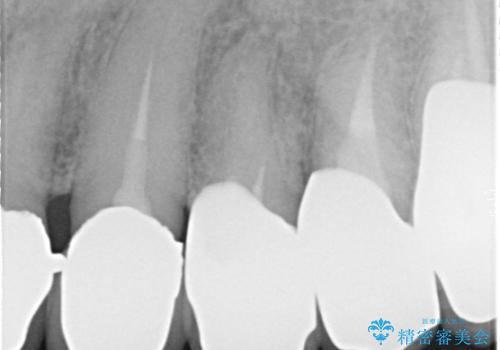

- 奥歯がなくて咬めないのと、全体的に見た目をよくしたいとのことで来院されました。

下顎の両側の奥歯が欠損しており、入れ歯をお持ちでしたが、うまく咬めずにほとんど使用していない状態でした。

上顎は全体的にクラウンの入れ替えと、下顎はインプラントの提案もしましたが、希望されなかったのでノンクラスプデンチャーの製作をする治療計画としました。

奥歯が欠損しており、上下の前歯が強く咬合する可能性があったので、上顎前歯の裏側は金属のものにしました。